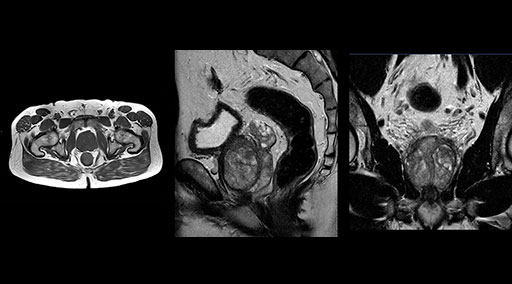

Patrick Duffy BS, RT (R) MR is Lead Technologist at DMG. “We are getting phenomenal image quality on all types of exams,” he says. “Our MSK is stellar, and so is our abdominal work. Ingenia excels at feet, hands and fingers. We do enterographies with great results. With the combination of the 3.0T magnet and the digital coils, we are able to scan prostates without an endorectal coil while still obtaining high quality results. This is a comforting experience for our male patients. We scan many obese patients, and the Ingenia does a tremendous job because of MultiTransmit, which reduces dielectric shading for more confident diagnosis. Our technologists really enjoy scanning on the Ingenia. We also have ordering physicians who specifically want their patients scanned on the Ingenia because of the results of our imaging.

“Without using an endorectal coil we do our prostate MR at 0.5 mm resolution, following the European society of urology protocol [1]. For certain joints we use a virtual arthroscopy protocol with 1 mm pixel size and 2 mm slice thickness. Ingenia really excels in our neurography, brachial plexus and prostate scans. Our neurologists insist on using our 3.0T for those,” Dr. Kaakaji adds.

“Our DMG Lisle location includes a cancer center, so soft tissue neck scans, brachial plexus scans, and prostate scans are common. For these exams, mDIXON TSE provides excellent images with and without fat suppression all while helping us reduce repeats and work more efficiently,” Mr. Duffy says.

“mDIXON TSE raises our diagnostic confidence with its homogeneous

fat suppression. Neck exams and rheumatology patients are two examples where mDIXON TSE is especially useful,” Dr. Kaakaji says. “For us it’s also an efficiency boost in exams where we need pre and post T1-weighted images with great fat suppression.”